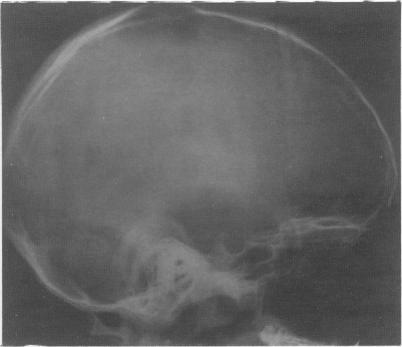

We studied eight patients with indolent gliomas. In all eight cases, despite characteristic radiological features, there was a delay in diagnosis because of misinterpretation of the initial computed tomogram. These tumours are an important cause of epilepsy of childhood, and surgery may well alleviate the epilepsy and possibly achieve a long term 'cure'. Therefore it is important that a diagnosis is made early and the lesion completely excised.